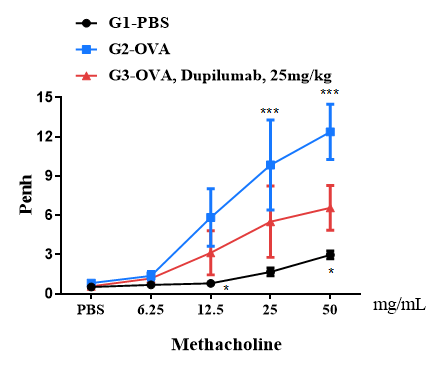

Airway responses following the exposure to increasing doses of methacholine (MCh) were measured for each mouse 24h after the final allergen or PBS exposure using the whole-body plethysmography. The y-axis represents the Penh absolute value. Increasing doses of methacholine were administered by aerosols.

B-hIL4/hIL4RA mice (BaIb/c)